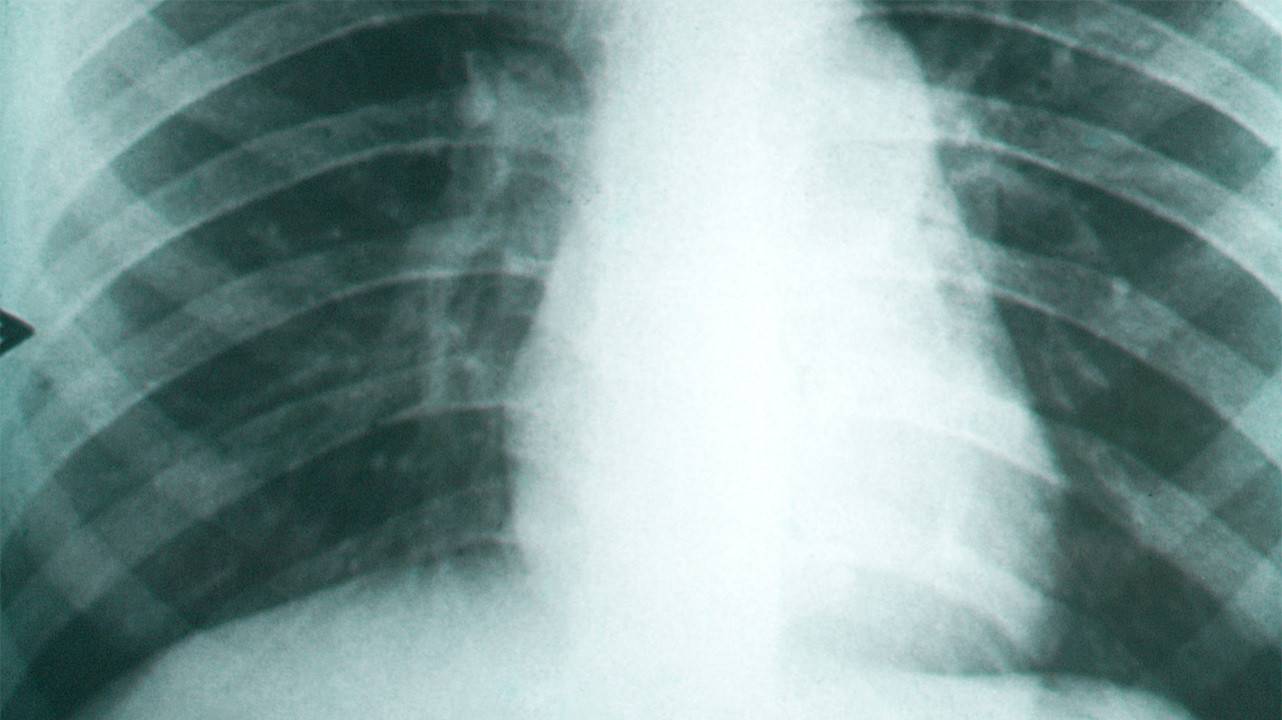

Кокцидиоидоз наиболее распространен в США (ежегодно заболевают около 100 тыс. человек) и в странах Латинской Америки. Заражение кокцидиоидом происходит при вдыхании пыли, содержащей споры гриба, или через поврежденную кожу. Заболевание протекает с тяжелыми поражениями кожи (образуются абсцессы и язвы) и внутренних органов (особенно легких) и может приводить к смертельному исходу.

Фиброз легких, вызванный кокцидиоидомикозом. Фото: PHIL CDC

Фиброз легких, вызванный кокцидиоидомикозом. Фото: PHIL CDC

Возможные осложнения